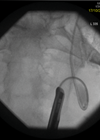

In the sixth article in this series the authors describe endourology nightmares involving ileal conduits and calculi. Case 1 A 69-year-old man who had a cystectomy and ileal conduit for muscle invasive bladder cancer, presented with an acute kidney injury...